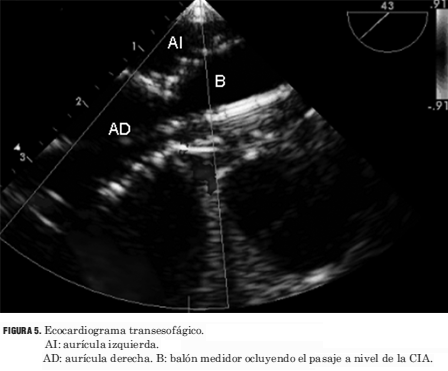

Todos los procedimientos se realizaron bajo anestesia general. En todos los casos se utilizó la vía venosa femoral. Se realizó la medida de la presión arterial pulmonar y cálculo de relación QP/QS (flujo pulmonar/flujo sistémico) mediante oximetrías. Se efectuó angiografía de vena pulmonar superior derecha en oblicua anterior izquierda con la finalidad de determinar las características anatómicas de la CIA y del séptum interauricular (figura 3). Posteriormente se efectuó la insuflación de un catéter balón medidor, con medio de contraste diluido (figura 4), posicionado a nivel del defecto interatrial hasta que cesa el flujo a su través, valorado por el Doppler color en el ETE (figura 5). Ello permite realizar la medida del diámetro de la CIA y elegir el diámetro del dispositivo. Los dispositivos utilizados fueron en tres casos el Cardioseal y en 72 el Amplatzer ASO. Todos los procedimientos fueron realizados con ETE simultáneo con el que se verificó la correcta ubicación del dispositivo antes y después de su liberación, y se descartó el compromiso de estructuras vecinas (figuras 6 y 7).

Figura 5. Ecocardiograma transesofágico. AI: aurícula izquierda. AD: aurícula derecha. B: balón medidor ocluyendo el pasaje a nivel de la CIA.